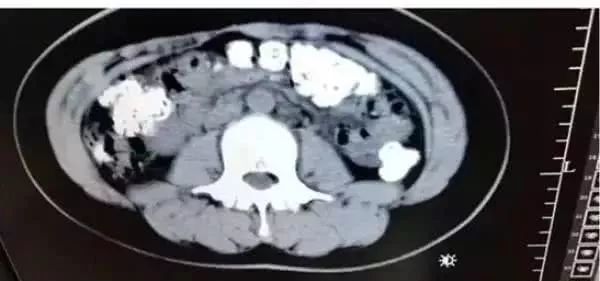

14岁女孩从胃肠到肛门密密麻麻...

来自浙江的女孩小沈(化名),在父母的陪同下来到浙江诸暨市人民医院急诊。小沈跟医生说自己肚子疼,有好几天无法排便,也吃不下东西。

于是,在医生的安排下,小沈做了腹部的CT。本来以为是普通的肠胃病,可没想到检查结果,让医生一惊:

患者胃部、横结肠、升结肠

降结肠、乙状结肠

一直到肛门

全都是颗粒状阴影

足足有百余颗之多

这么多颗粒状阴影究竟是什么东西呢?在医生的问询下,患者小沈才道出了实情。原来小沈5天前喝了一杯珍珠奶茶,而喝下去的珍珠,没有被消化掉,堆积在小沈的肠胃处。